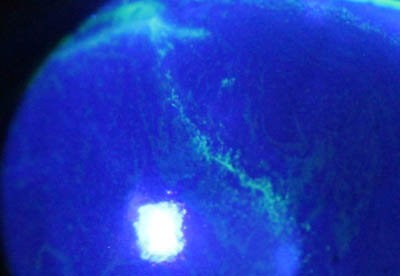

Perineuritis

No tienen los bulbos terminales de las dendritas del Herpes Simple

Formación de lineas epiteliales elevadas que pueden dar la imagen de Seudodendrítas

Formación de lineas epiteliales elevadas que pueden dar la imagen de Seudodendrítas + Perineuritis